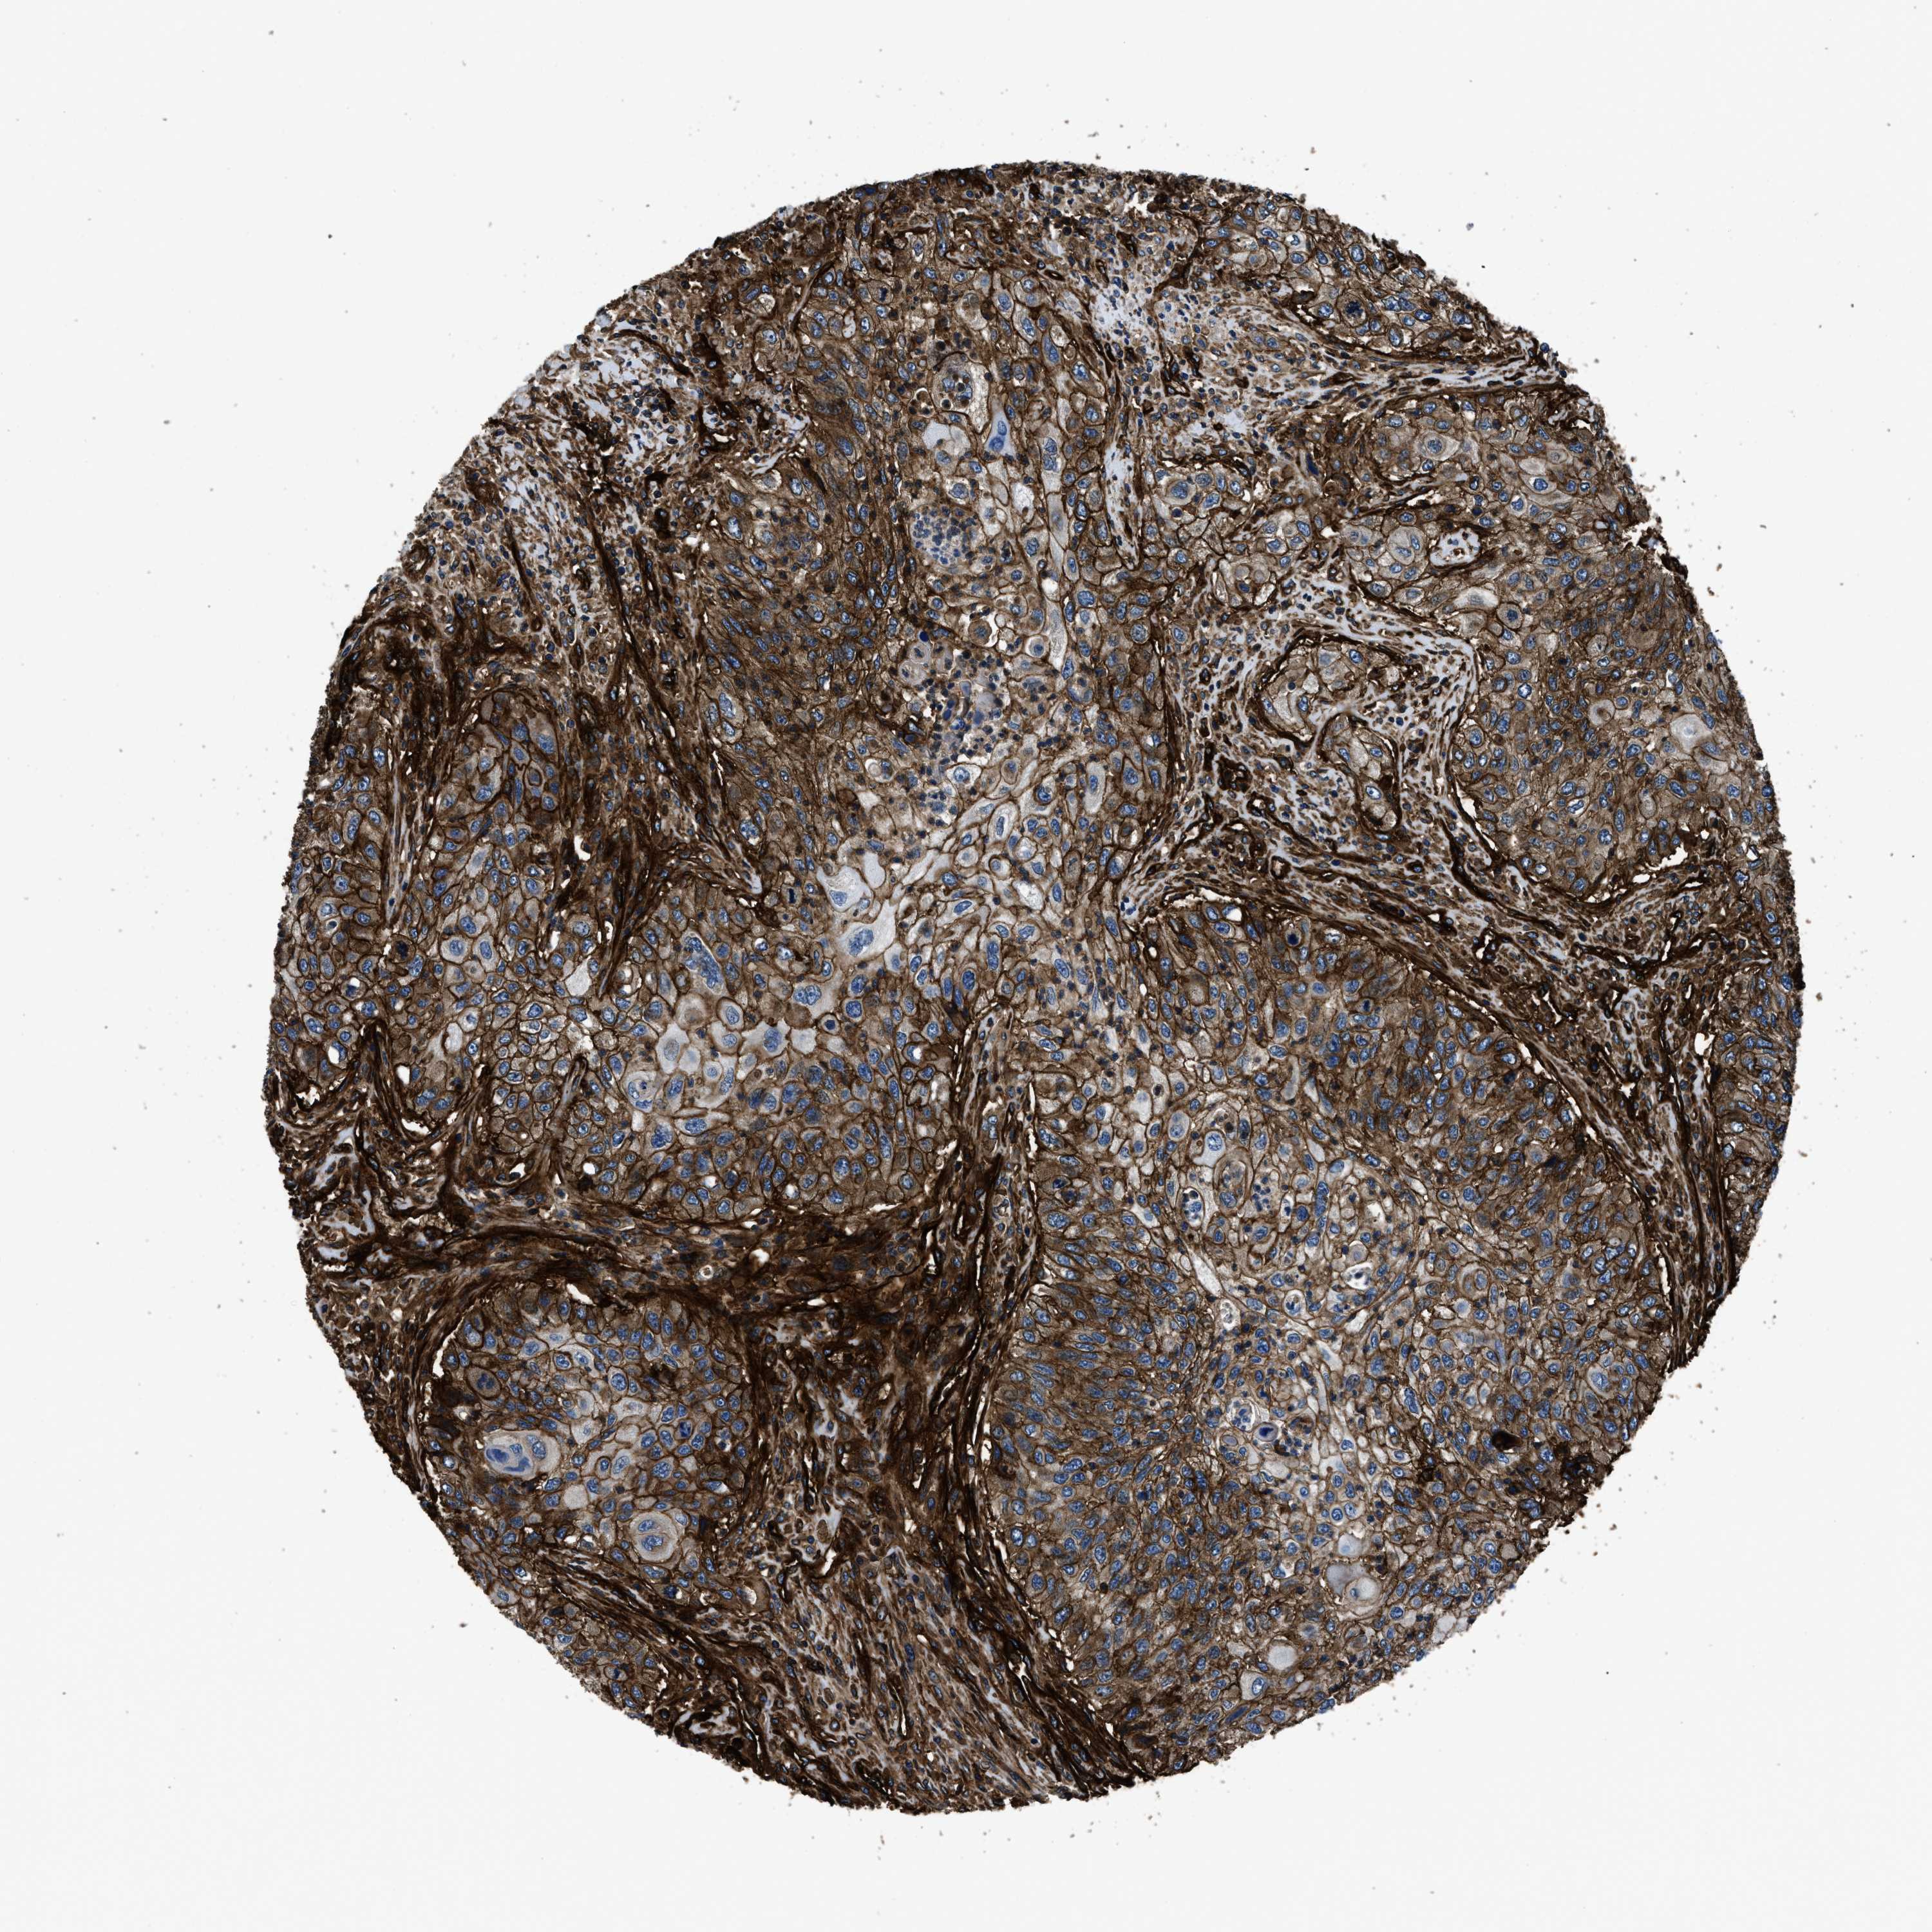

UROTHELIAL CANCER - Protein expressioni

A mouse-over function shows sample information and annotation data. Click on an image to view it in a full screen mode. Samples can be filtered based on level of antibody staining by selecting one or several of the following categories: high, medium, low and not detected. The assay and annotation is described here.

Note that samples used for immunohistochemistry by the Human Protein Atlas do not correspond to samples in the TCGA dataset.

Antibody stainingi

Antibody staining in the annotated cell types in the current human tissue is reported as not detected, low, medium, or high, based on conventional immunohistochemistry profiling in selected tissues. This score is based on the combination of the staining intensity and fraction of stained cells.

Each image is clickable and will lead to virtual microscopy that enables deeper exploration of all samples and also displays staining intensity scores, fraction scores and subcellular localization as well as patient and tissue information for each sample.

Antibody HPA009285

Antibody HPA017139

Antibody CAB017826

Staining

High

Medium

Low

Not detected

Intensity

Strong

Moderate

Weak

Negative

Quantity

>75%

75%-25%

<25%

None

Location

Nuclear

Cytoplasmic/membranous

Cytoplasmic/membranous,nuclear

Urothelial carcinoma, Low grade

Urothelial carcinoma, High grade